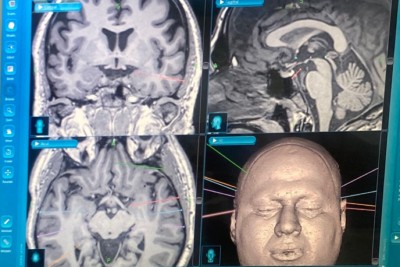

الأولى في الشرقية.. زراعة ”أقطاب“ داخل دماغ أربعيني

أجرى فريق طبي من مركز العلوم العصبية في مستشفى الملك فهد التخصصي بالدمام، عملية صرع نوعية لمواطن في العقد الخامس من العمر، في عملية جديدة تمت من خلال التدخل الجراحي المحدود باستخدام.StereotacticEEG وتعد الأولى من نوعها في المنطقة الشرقية. وأوضح رئيس تشغيل مستشفى الملك فهد التخصصي بالدمام شريف عمر أن العملية تمثلت في زراعة حساسات رفيعة وعميقه داخل الدماغ وذلك بإدخالها عن طريق فتحات في الرأس لا يتجاوز قطرها 3 مليمتر. وأضاف: ... |